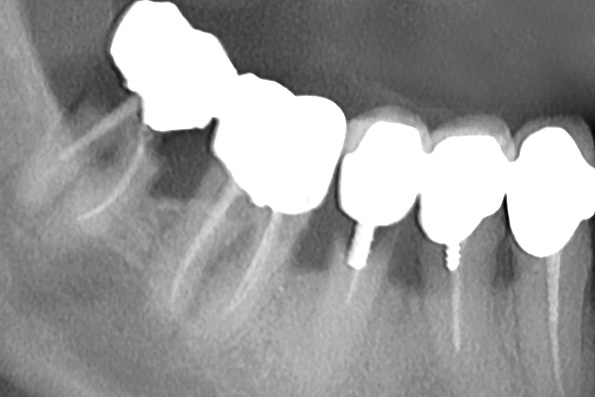

Multiple socket preservation in the mandibular with collacone® max – Dr. D. Jelušić